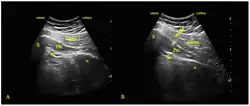

Ultrasound scan (left) and ultrasound-guided injection (right) of the piriformis muscle. Gmax = gluteus maximus; Pm = piriformis muscle; sn = sciatic nerve; S = sacrum; H = hip bone.

Injections are part of multi-modal therapy and can be therapeutic.[29][2] They may be used with conservative treatments like physical therapy or after the failure of conservative treatments. Injections deliver medication directly to the piriformis muscle through a needle. The needle is placed into the piriformis muscle with image guidance such as fluoroscopy, ultrasound, CT, or MRI.[2][30] Ultrasound is a popular choice due to a balance of accuracy, accessibility, lack of radiation exposure, and affordability.[29][2]